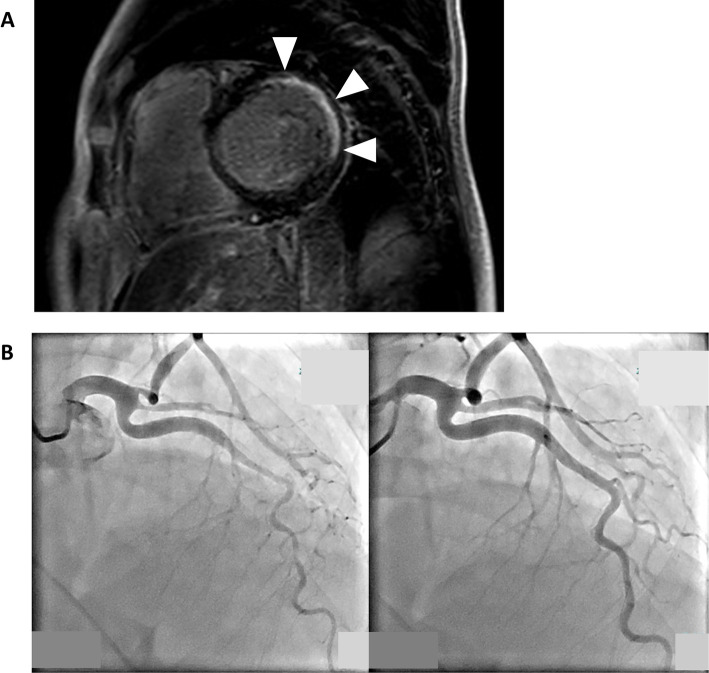

Coronary artery spasm (CAS) is an underrecognized cause of heart failure, even in the absence of obstructive coronary artery disease. We report three cases of heart failure in which CAS was identified as the critical etiology. All patients exhibited symptoms of heart failure with nonobstructive coronary arteries, and CAS provocation testing confirmed epicardial spasm. In two cases, cardiac magnetic resonance imaging revealed ischemic patterns consistent with CAS-related injuries. Calcium channel blockers effectively stabilize the signs and symptoms related to heart failure. This series highlights CAS as a contributor to heart failure progression and emphasizes the importance of provocation testing and early tailored therapy for improving outcomes.

Abstract Image